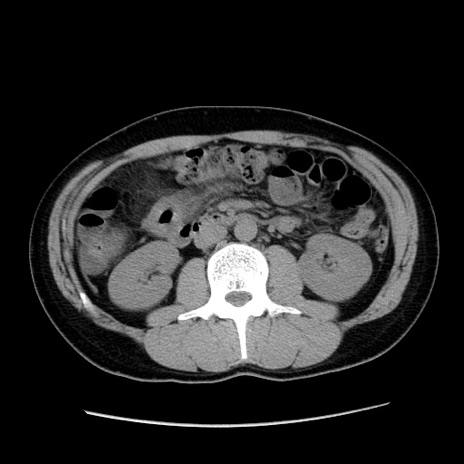

症例36(横断像)

【症例】20歳代 男性

【主訴】心窩部痛

【現病歴】今朝より上腹部痛あり。一旦軽快していたが再度出現したため救急要請。昨日夕に白身の魚を含む刺身を食べた。

【身体所見】BP 136/89mmHg、HR 74/min、BT 37.0℃、腹部:膨満、軟、心窩部に圧痛あり。反跳痛なし、筋性防御なし、腸雑音やや亢進あり。

【データ】WBC 17700、CRP 0.48